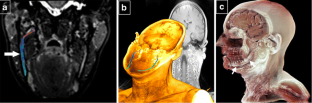

Chhabra A, Carrino JA, Farahani SJ, Thawait GK, Sumner CJ, Wadhwa V et al (2016) Whole-body MR neurography: Prospective feasibility study in polyneuropathy and Charcot-Marie-Tooth disease. J Magn Reson Imaging 44:1513–1521